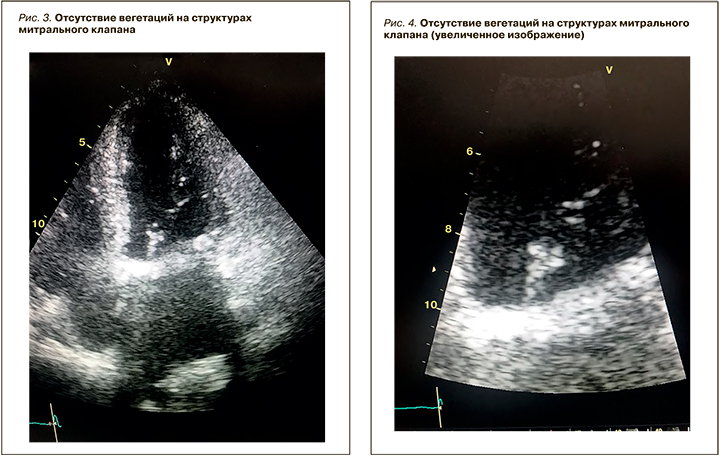

На 10-й день пребывания в стационаре (22.11.2019) при ЭхоКГ, проведенном в рамках диагностического поиска генеза лихорадки, впервые были выявлены два дополнительных образования на деформированном митральном фиброзном кольце и подклапанных структурах митрального клапана (рис. 1, 2). Одно из них было подвижным и пролабировало в полость левого предсердия, округло-продолговатой формы, размерами 1,4×0,8 см. Также определялся выпот над правым предсердием с сепарацией листков перикарда до 0,5 см как проявление полисерозита в рамках системной воспалительной реакции.

В стационаре проводился мониторинг ЭхоКГ каждые 7 дней и на 32-й день терапии. При контрольной ЭхоКГ исчезли вегетации на митральном клапане (рис. 3, 4), уменьшился объем правого предсердия и несколько снизилось систолическое давление в легочной артерии, исчез выпот в полости перикарда.